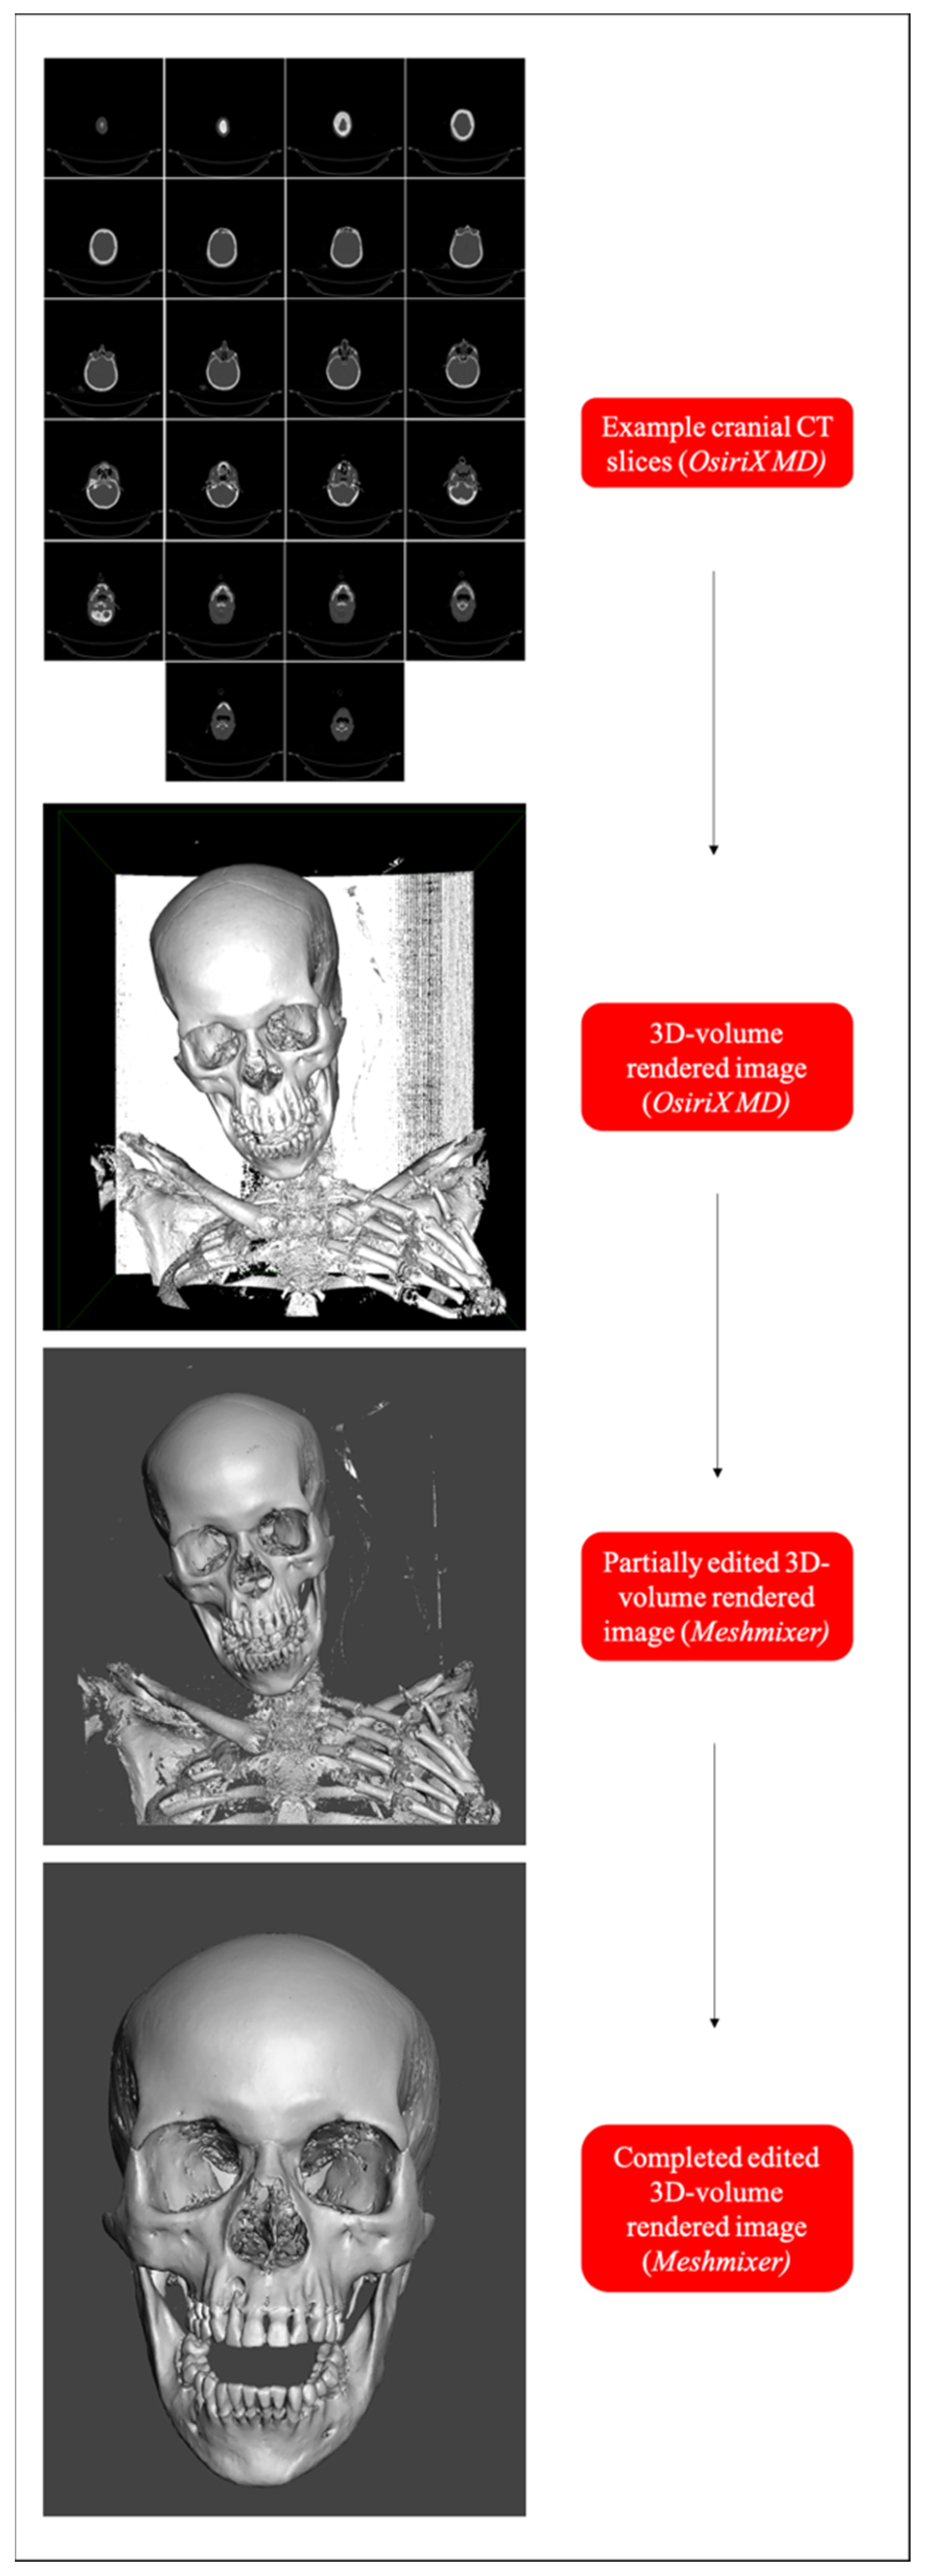

2.2. Study Sample Preparation and Data Collection

4.5. Data Collection from 3D-VR CT Images